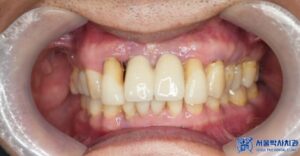

보철물 재제작 후 사진입니다.

제거 후 보철물 제작까지

단 2일 만에 치료를 마무리 하였으며,

환자분께서도 심미적으로

매우 만족해 하셨습니다.